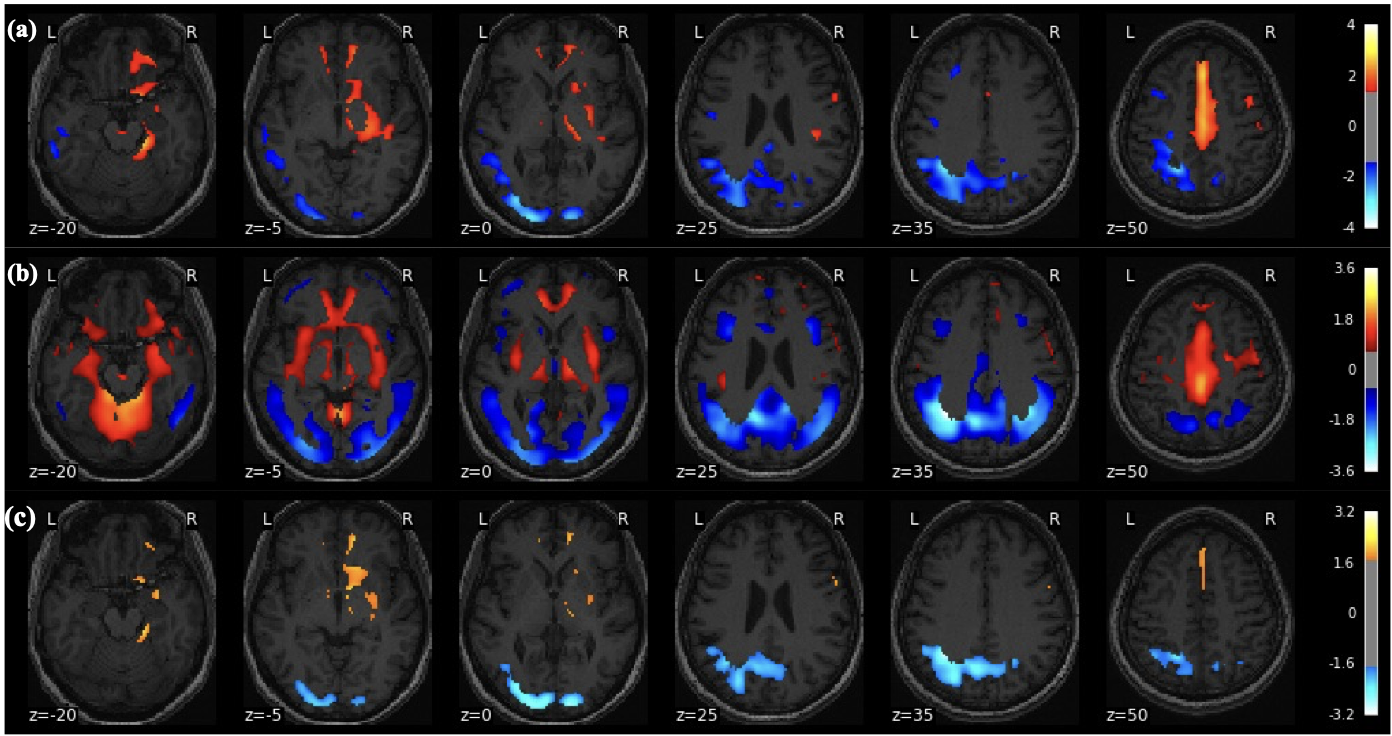

There were no significant differences in age (p = 0.104) and gender (p = 0.276) between the PD and HC. The perfusion PDRP based on ASL images is shown in Fig.1a. The PDRP network consisted of a linear combination of PC1 (vaf = 19.8%, β = 1.06, p = 0.003), PC2 (vaf = 12.7%, β = 1.09, p = 0.002) and PC4 (vaf = 4.8%, β = 1.28, p = 0.017). The metabolic PDRP based on FDG-PET images is shown in Fig. 1b, in which PC2 (vaf = 11.0%, β = 1.43, p = 0.001) and PC3 (vaf = 6.5%, β = 1.13, p = 0.011) were selected.

The PC1 (vaf = 19.8%, β = 0.83, p = 0.009), PC2 (vaf = 12.7%, β = 0.80, p = 0.017), and PC4 (vaf = 4.8%, β = 1.31, p = 0.009) selected in ASL data and PC2 (vaf=11.0%, β = 1.32, p = 0.023) selected in FDG-PET data were combined to form the metabolism-perfusion fusion PDRP Fig. 1c.

The PET-derived pattern and ASL-derived pattern were consistent with previous work 3, 4. Both PDRPs showed the patterns with increased CBF/metabolism (red) in the deep grey matter and with decreased CBF/metabolism (blue) in the occipital regions. However, FDG-PET PDRP had a more symmetric pattern for the occipital and deep gray matter regions and higher metabolism in the cerebellum region, compared to the ASL PDRP.

Figure 1. Parkinson's disease related pattern and associated scores. PDRP network pattern of ASL (a), PET (b), and multimodal ASL-PET (c). The Zscores were presented by the colorbars.